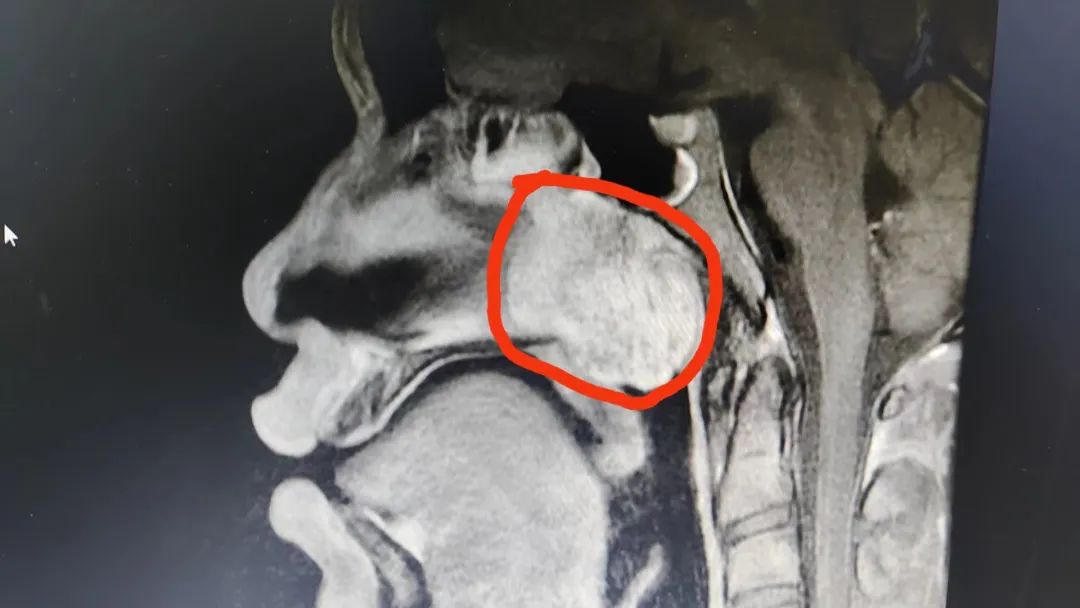

「经鼻窦 MRI 进一步检查,发现小余鼻咽部有一块肿瘤,直径约 4.5 厘米,完全堵塞后鼻孔,范围广泛,累及翼腭窝、颞下窝等颅底组织。这样大范围侵及颅内的鼻咽纤维血管瘤在临床中较少见。」佛山市三水区人民医院耳鼻喉科负责人陈裕光副主任医师表示,鼻咽纤维血管瘤是一种富含无止血功能血管团的良性肿瘤,容易导致大出血,不及时手术随时都会大出血危及生命。

术中先解剖出肿瘤的主要供血血管并离断止血,再精准、完整地切除肿瘤,避免术前介入栓塞止血,大大节省了患者费用。手术经过六小时顺利完成,切除了 4.5*4*3 cm 类圆形肿物,术中出血少、创伤小,目前患者恢复良好。